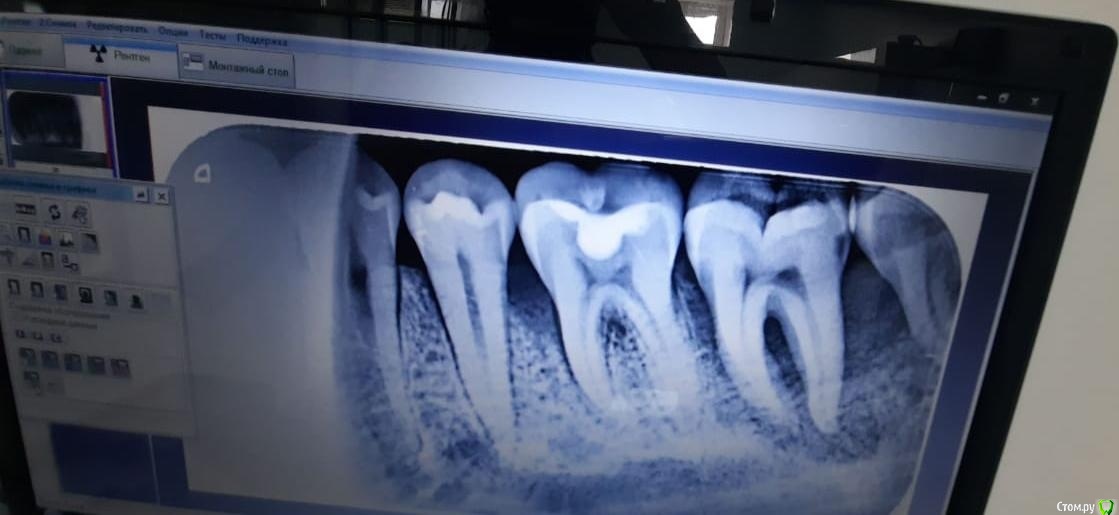

magasobaka Опубликовано 1 октября, 2020 Поделиться Опубликовано 1 октября, 2020 (изменено) Пациенту 21 год.37 интактный, вокруг воспаление, подвижен. Не камня, не налёта во рту нет, всё идеально чисто.В хирургии сказали удалить. Возможно такой зуб сохранить? Изменено 1 октября, 2020 пользователем magasobaka Ссылка на комментарий

vse32 Опубликовано 2 октября, 2020 Поделиться Опубликовано 2 октября, 2020 Вероятно это какой-то генирализованый процесс. У 36 медиально так же уже есть карман. Возможно наследственный. Опросите на предмет как дела с зубами у ближайших родственников. Видела такие генирализованные проблемы у людей лет 40 и старше. Но там уже практически все было в таком состоянии. Все под удаление. Причину не назову, но однозначно надо проверять на сахар, на гормоны щитовидки. Может еще чего. Подождем еще мнения коллег. Холодная вода летом, думаю, не причем. Ссылка на комментарий

St. Опубликовано 2 октября, 2020 Поделиться Опубликовано 2 октября, 2020 Если бы был невитальный, то шанс был бы чуть лучше, но все равно не очень.Если же живой - это чистая периопроблема и прогноз очень плохой. Удалять Ссылка на комментарий

annda Опубликовано 4 октября, 2020 Поделиться Опубликовано 4 октября, 2020 (изменено) Окклюзионные контакты посмотреть, смещающие( как правило скаты язычных бугров) спилить, опорные( вершины щечных бугров) заузить до точки, если на них площадки.Нагрузку эти зубы не вывозят, выраженный окклюзионная форма говорит о том, что эмаль с дентином не стираются, а пародонт убивается. Клинчер или бруксист. Каппу на ночь.Я бы 8ку убрала еще, там такая пещера для налета. Зашинировать моляры . Сколько - то потянет. Изменено 4 октября, 2020 пользователем annda Ссылка на комментарий